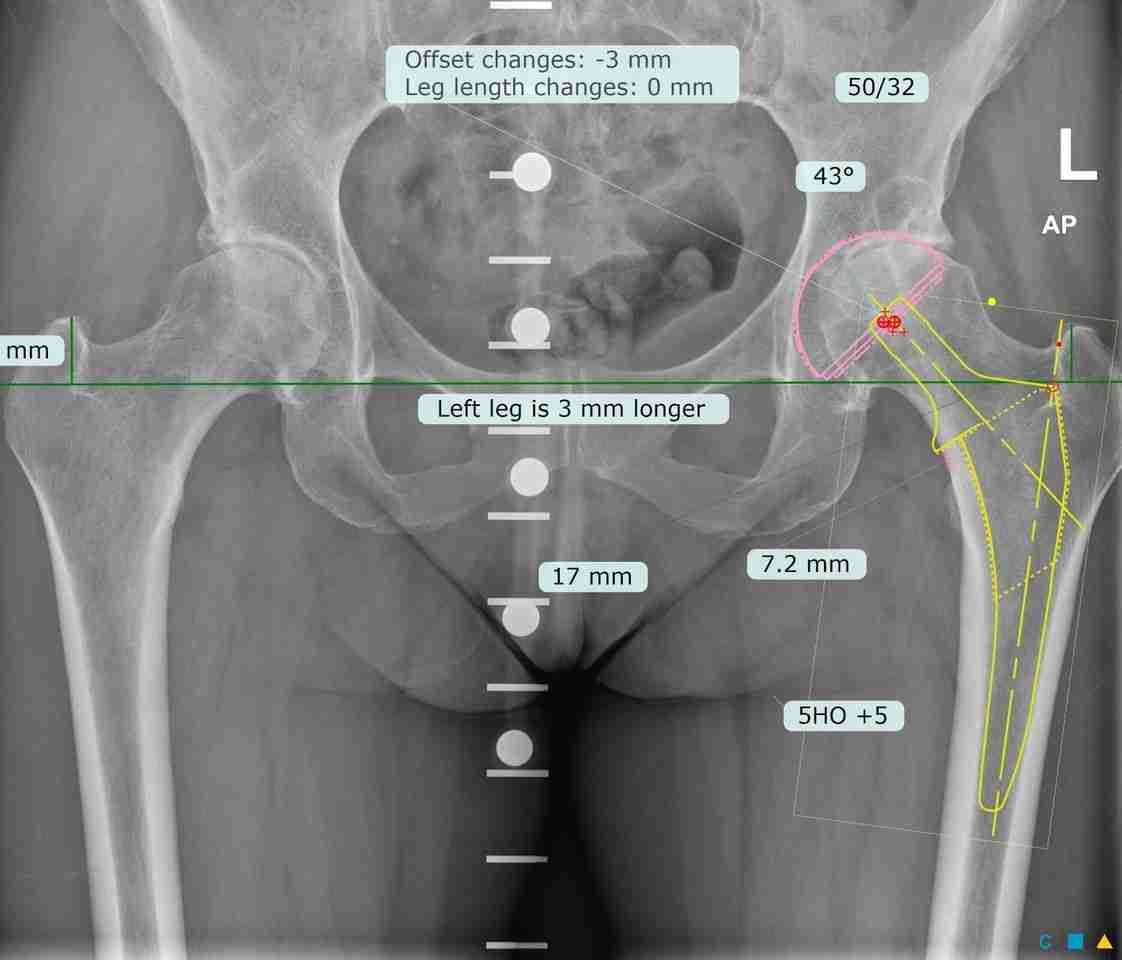

- Radiografías para evaluar el estado de la articulación de la cadera.